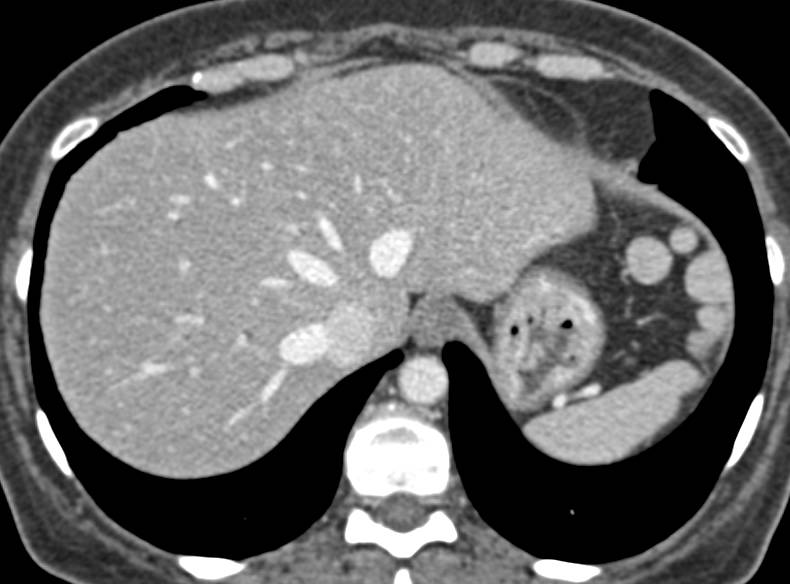

Splenic Infarct